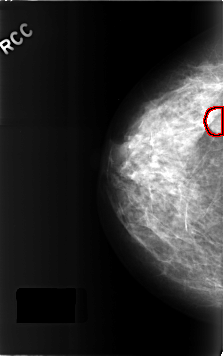

C_0308_1.RIGHT_CC

RIGHT_CC LINES 4616 PIXELS_PER_LINE 2904 BITS_PER_PIXEL 12 RESOLUTION 50 OVERLAY

FILE: C_0308_1.RIGHT_CC.OVERLAY

TOTAL_ABNORMALITIES 1

ABNORMALITY 1

LESION_TYPE MASS SHAPE ROUND MARGINS CIRCUMSCRIBED

ASSESSMENT 3

SUBTLETY 4

PATHOLOGY BENIGN

TOTAL_OUTLINES 1

BOUNDARY